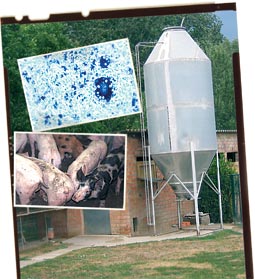

Le diagnostic différentiel de la MAP peut être compliqué et ne s’entend qu’à l’échelle d’un élevage, puisqu’au plan individuel, un seul animal peut ne pas présenter tous les signes déterminants sur lesquels se fonde la définition de la maladie (voir ci-dessous).

Le diagnostic différentiel dépend du signe clinique dominant dans l’élevage, et, dans tous les cas, doit envisager toutes les maladies qui entraînent un amaigrissement.

La forme respiratoire du SDRP est l’entité clinique à inclure au premier rang de la liste du diagnostic différentiel. C’est la source la plus fréquente de confusion avec la MAP car le SDRP est présent dans la plupart des pays où la MAP existe aussi, ce qui rend la distinction entre l’une et l’autre maladie délicate au plan clinique. À nouveau, une série de tests diagnostiques de laboratoire s’impose.

La définition proposée d’un élevage atteint de MAP (voir le chapitre “diagnostic de troupeau”) n’a pas la prétention d’être unique, mais est consensuelle au moins en Europe, et prend en compte des critères aisés à mettre en application..

Un vaccin contre le PCV2 est disponible sur le marché, dans l’objectif de contrôler la MAP. Comme cette maladie présente une symptomatologie clinique assez peu spécifique (beaucoup d’autres maladies provoquent un amaigrissement du porc), son diagnostic précis est fondamental pour établir les critères objectifs de prescription du vaccin.